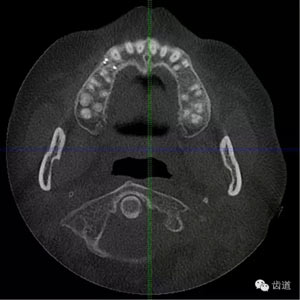

好的開(kāi)始就是成功的一半。通過(guò)CBCT了解根管的位置,形態(tài),方向。

檢查顯示:近頰及腭根充填恰填,遠(yuǎn)頰根管內(nèi)有少許充填物影像。根尖明顯低密度影像。